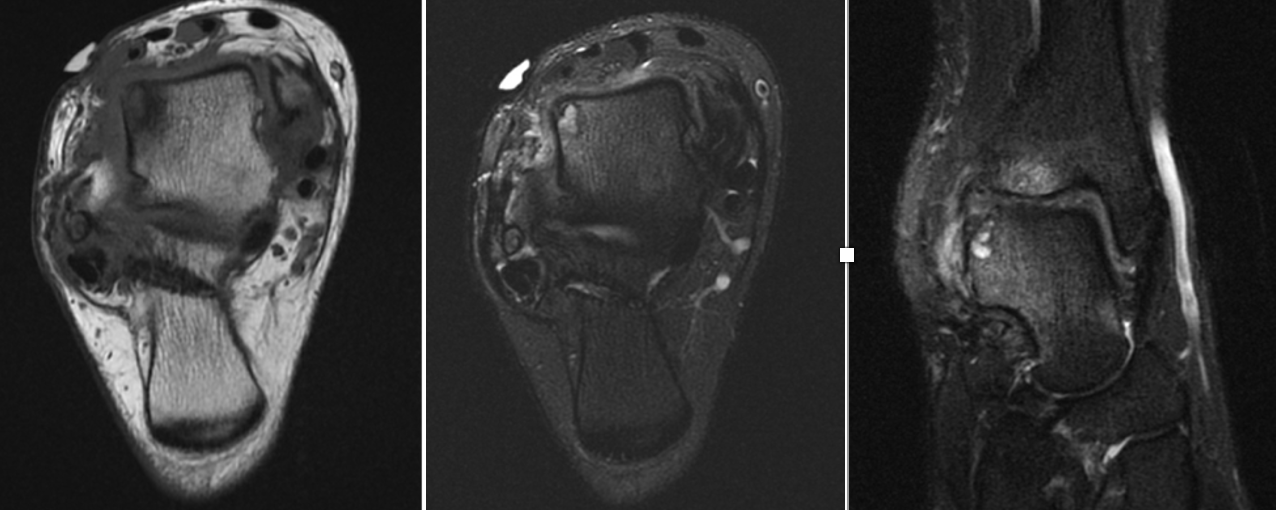

We presented the option of a patient-specific partial talar replacement with a plan to resect and replace the entire lateral shoulder. As part of the design process, the implant had custom cut guides that would sit on the talar neck, temporarily secured in place with smooth wires. This guide would then correlate with the final implants to ensure the appropriate amount of bone removal and allow more accurate bone resection. In addition, the design incorporated two stems in the final implant to add stability and fixation surface area. Three sizes of implant allowed intra-operative flexibility.

The incision was the typical anterior ankle approach. This would limit location of incisions for potential future issues or conversion to fusion or total implant. We then exposed the distal tibia and dorsal neck of the talus. Placing the prefabricated custom cut guide onto the neck of the talus, we then checked this under fluoroscopy to ensure placement, and the proper orientation and amount of lateral dome to be removed. We then pinned this guide in place with predetermined holes. A reciprocating blade limited blade excursion and minimized potential for injury to adjacent structures. After removal of the damaged piece of talus we placed the trials. The goal was to have the trial flush or even slightly recessed with regard to the adjacent cartilage. During weight bearing, the native cartilage will compress, so it is important to match the weight bearing level. If the implant is proud, then during weight bearing the cartilage will naturally compress, but the implant will not, potentially giving rise to issues with load bearing around the device.